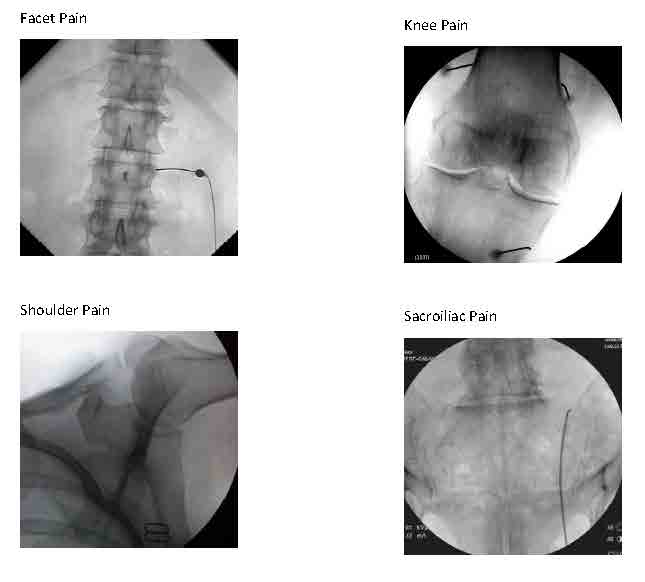

We can diagnose and treat lumbar facet joint pain due to spondylosis similarly, either with a steroid injection into the joint (intra-articularly) or by blocking small nerves to these joints (medial branch blocks) with local anesthetic diagnostically and, if warranted, with RFA therapeutically (as a treatment).

We can use these same approaches to treat facet pain in the neck less frequently and in the midback rarely.

Other procedures using fluoroscopic guidance are evolving. Genicular nerve blocks that involve the usual 2 sets of diagnostic anesthetic blocks followed by blocks with RFA can be very helpful in patients with knee osteoarthritis that is either inoperable or has already failed knee joint replacement surgery. RFA nerve blocks to other joints such as the shoulder and hip for osteoarthritis are in development.